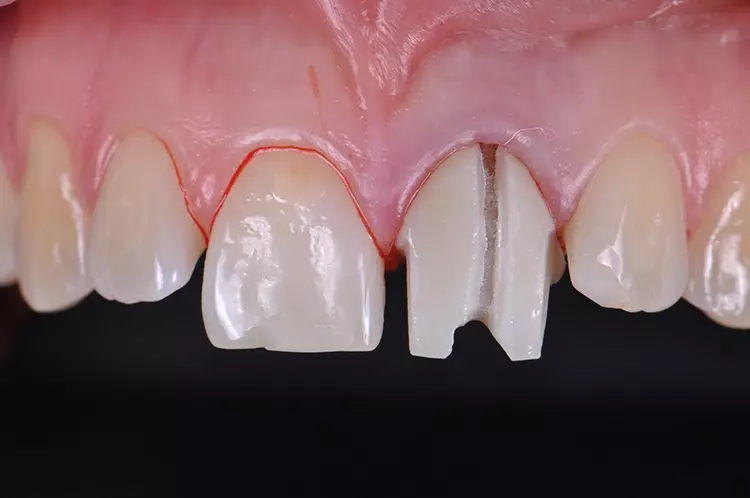

Im Rahmen des Erstgespräches berichtete die junge Patientin von einem Sturzereignis, bei dem der Schneidezahn frakturierte. Ihr damaliger Zahnarzt führte eine Wurzelkanalbehandlung durch und versorgte den Zahn mit einer Krone aus Lithiumdisilikat. Das anfänglich sehr ansprechende ästhetische Behandlungsergebnis hätte sich jedoch nach der Eingliederung mit der Zeit verändert und die Patientin stellte eine zunehmende Verfärbung der Frontzahnkrone fest (Abb. 2 und 3).

Dies kann aus einer nachträglich eingetretenen Verfärbung des devitalen Zahnes resultieren. Durch die sehr hohe Transluzenz der Glasphase einer Lithiumdisilikat-Restauration kann die dunkle Stumpffarbe durchschlagen und zu einem ästhetisch störenden „Grauschleier“ führen. In einem intensiven Beratungs- und Aufklärungsgespräch wurden der Patientin die Schwierigkeiten und Herausforderungen einer Einzelzahnkrone in der ästhetischen Zone bei einer hohen Lachlinie mit Exposition der Gingiva dargestellt.

Manche Details wie die Verfärbung der Gingiva wären nicht korrigierbar und verringerten die Vorhersagbarkeit eines optimalen ästhetischen Resultates. Die Neuversorgung dient der Verbesserung der ästhetischen Situation, eine perfekte Kopie des Zahnes 11 wird nicht zu erzielen sein, da die verfärbte Wurzel bestehen bleibe.